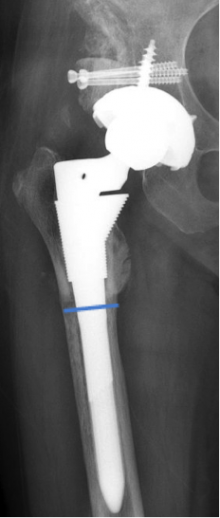

人工股関節再置換術

人工股関節は改良を重ね、徐々に耐久性は向上してきましたが、人工股関節のゆるみ、磨耗や感染等により、人工関節の入れ替え(再置換)の手術が必要となる可能性があります。人工股関節の最初の手術の年齢が若年者(40歳代、場合によっては30歳代にも)にも行われるようになり、平均寿命も延びていることから再置換を要する患者さんも今後増加すると考えられています。

再置換の場合は骨がうすくなっていたり、大きな骨欠損があったり、人工関節と骨を固定するために用いた骨セメントの摘出に困難を極める場合もあり、最初の手術より技術的に難しく、手術時間も長時間を要します。また、出血量も多くなる傾向にあります。